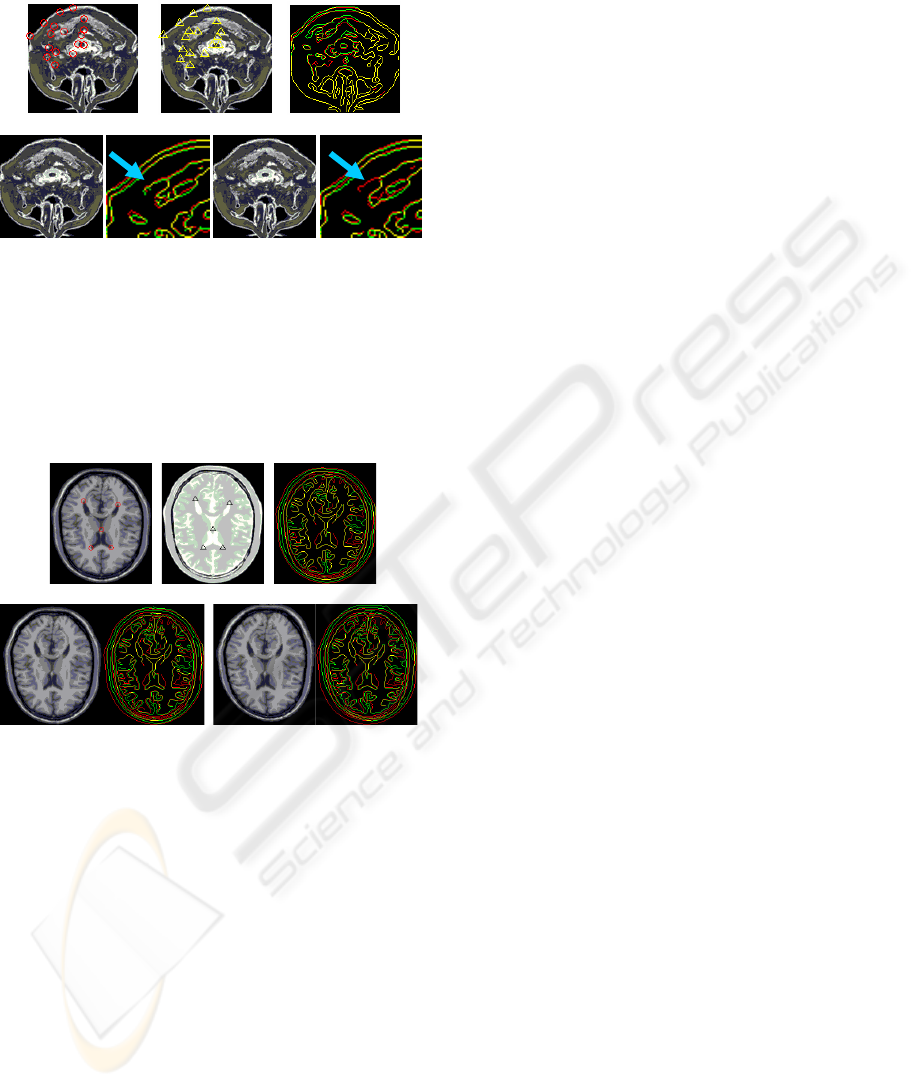

In Figure 5, we can compare the results of

deformation using CSTPF and CSRBF. They look

similar but definitely not the same. Observing their

edge comparison (Figure 5 (d) and (e)), it is revealed

that after deformation, figure 5(d) has more edge

information than figure 5(e) (as shown by the

arrowhead), which means more information was

saved by using CSTPF than CSRBF.

Finally, we employed another experiment to

demonstrate that global deformation using CSTPF is

better than CSRBF. In this experiment, we used an

image of deferent mode, figure.6 (a) is MRI image

and figure 6 (b) is CT image. It can be easily noticed

that the source image and target image are just the

same as they have no deformation. However,

because we get landmarks manually, it is liable to

have some artificial errors which are, however,

considered as allowable errors. Given that these